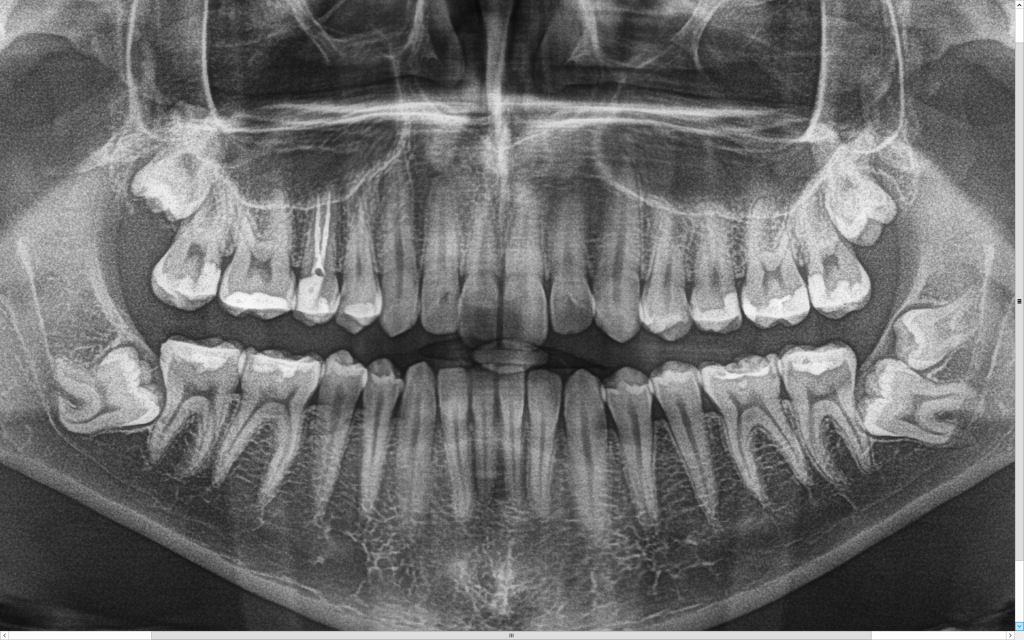

Z uwagi na moją specjalizację kierowani są do mnie pacjenci z tzw. zębami mądrości – ósemkami, które ze względu na ułożenie w kości wymagają operacyjnego usunięcia. Zdarzają się również pacjenci z mezjodensami (fot. 1,2) zębami nadliczbowymi np. dziewiątkami (fot.3), zębami zatrzymanymi (fot 4.), lub zębami zrośniętymi (fot. 5,6). Stomatolog z długą praktyką nie raz w swojej karierze zetknął się z takimi przypadkami.